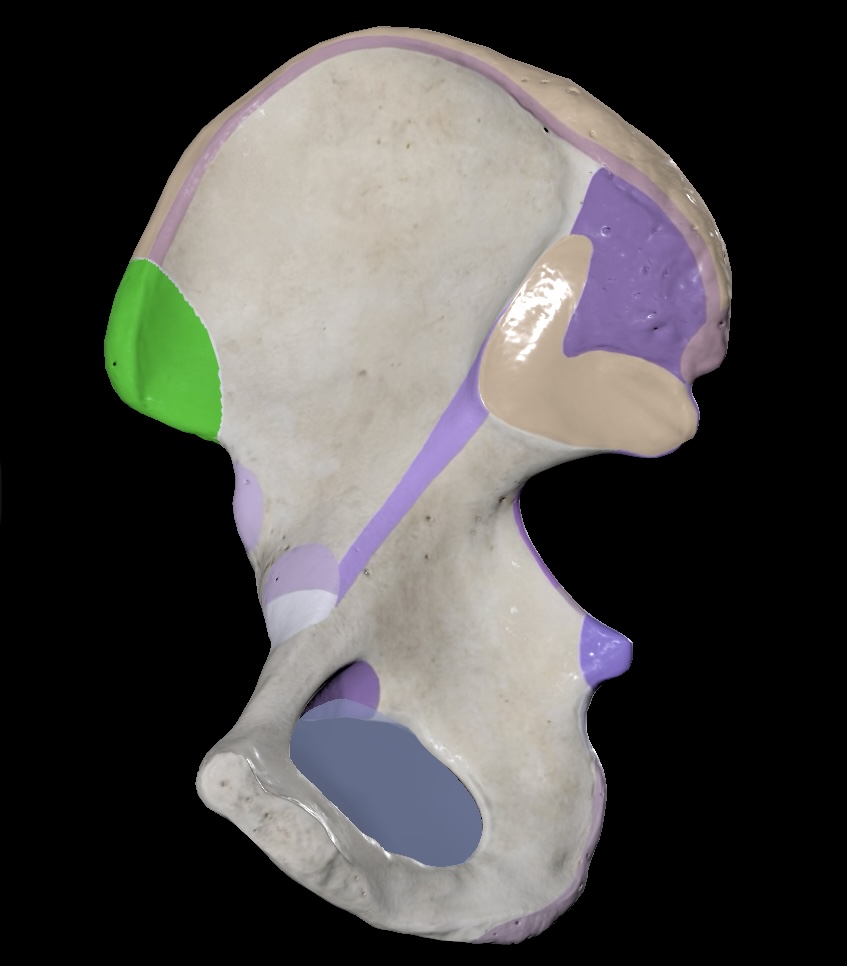

Illium

Ischium

Pubis

Ischial Spine of Ischium

Iliac Tuberosity of Illium

Anterior Superior Iliac Spine

Anterior Inferior Iliac Spine

Posterior Superior Iliac Spine

Posterior Inferior Iliac Spine

Iliac Crest

Acetabulum